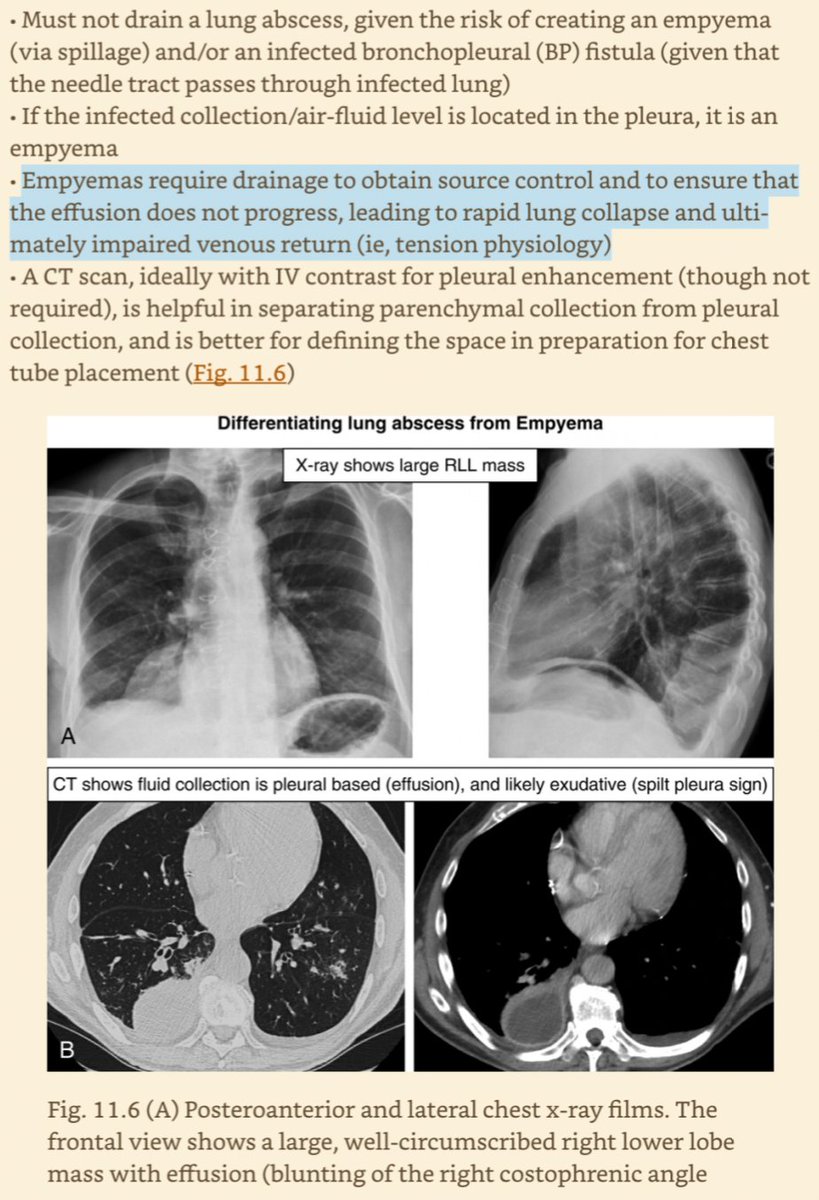

CXR shows:

🦠 Patchy, basilar, nodular, & round opacities (often +effusion)

🦠 Necrotizing PNA & Pseudo-necrosis (spillage into pre-existing cavity)

🦠 Abscess & Empyema (+hydropneumothorax if empyema)